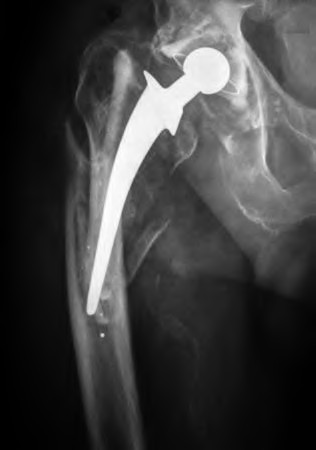

A 72-year-old female falls and sustains a periprosthetic femur fracture around her cementless total hip arthroplasty. Radiographs reveal a fracture extending just distal to the tip of the stem. The stem is radiographically loose, but there is excellent proximal and distal bone stock. According to the Vancouver classification, what is the fracture type and the recommended surgical treatment?

A patient presents with thigh pain 10 years after a cementless total hip arthroplasty. Radiographs demonstrate a continuous radiolucent line of 3 mm with sclerotic margins in Gruen zones 1, 2, 6, and 7. The stem has subsided by 5 mm. What is the most likely mode of failure?

A 75-year-old female sustains a fall 5 years after a cementless THA. Radiographs show a periprosthetic femur fracture occurring around the stem tip. Intraoperative assessment reveals the stem remains firmly fixed in the metaphysis, and the proximal bone stock is adequate. According to the Vancouver classification, what is the fracture type and the standard recommended treatment?

A 72-year-old female presents with acute thigh pain and an inability to bear weight after a minor fall, 10 years post-THA. Radiographs demonstrate a fracture around the tip of the well-fixed femoral stem, extending into the diaphysis. The bone stock proximally remains intact. Which principle must be strictly adhered to during the surgical fixation of this fracture?

A patient requires a femoral revision THA for aseptic loosening. Radiographs demonstrate extensive metaphyseal bone loss with the diaphyseal cortical bone remaining fully intact for only 3 cm distal to the tip of the current stem. According to the Paprosky femoral defect classification, what type of defect is present?

A 78-year-old female sustains a periprosthetic femur fracture 10 years after a cemented THA. Radiographs show a fracture around the tip of the stem with a loose femoral component and poor proximal bone stock, but adequate diaphyseal bone.